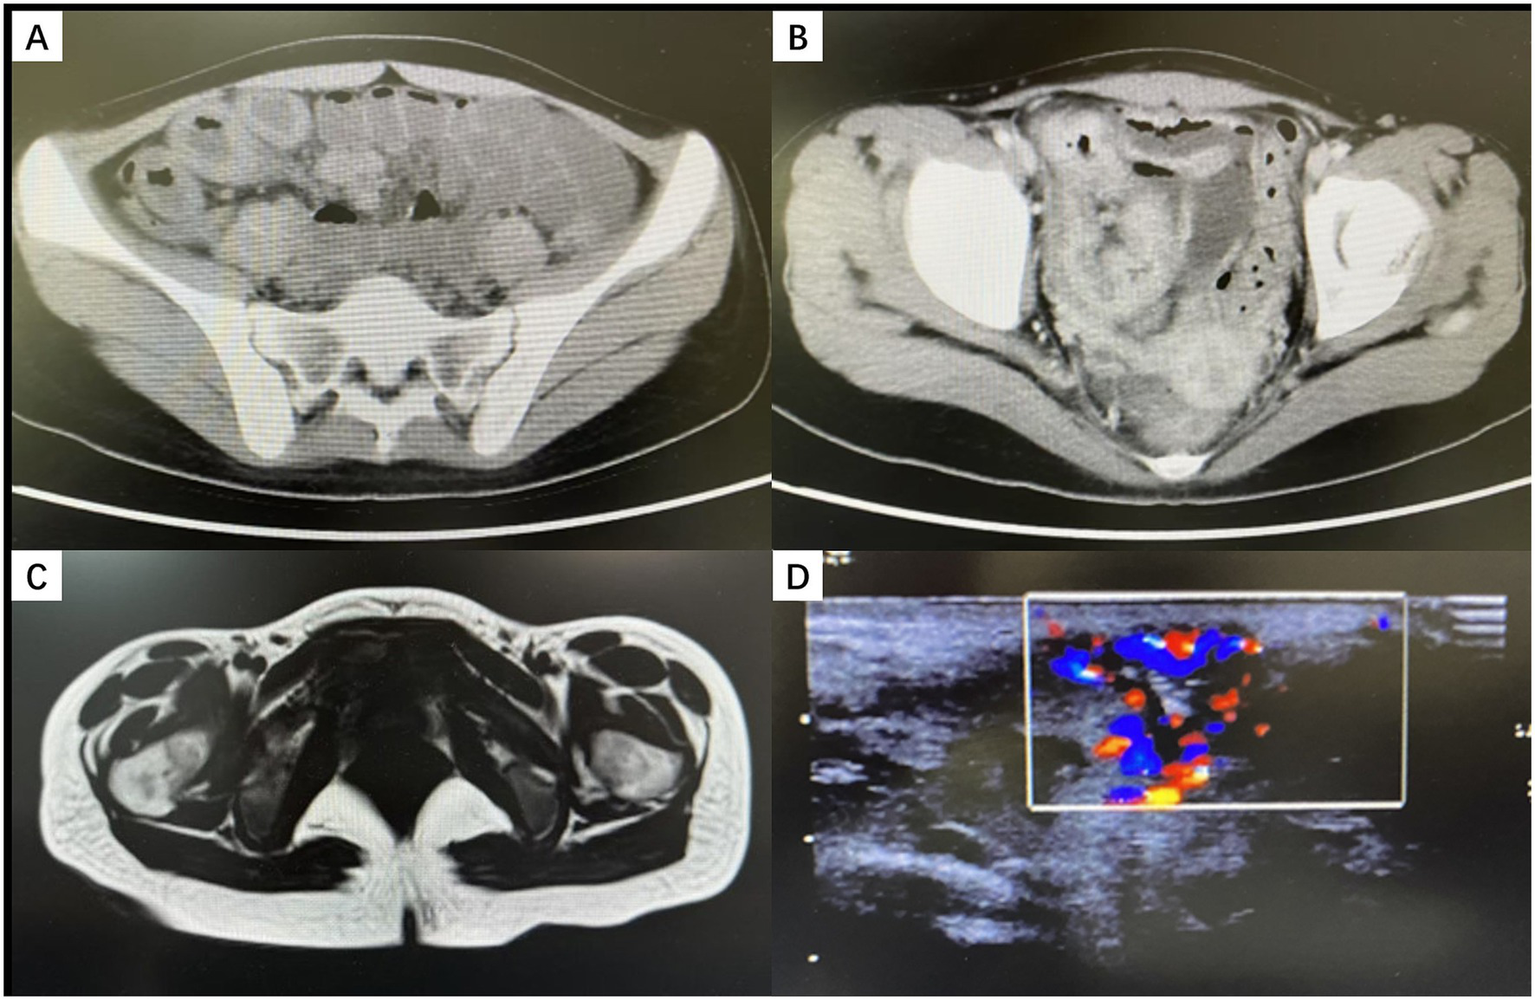

Imaging: Contrast-enhanced abdominal CT showed segmental thickening of the terminal ileum and adjacent bowel segments, accompanied by mesenteric lymphadenopathy (Figures 2A,B). Perineal ultrasound and pelvic MRI indicated a subcutaneous abscess cavity in the left vulva extending toward the anal canal and rectovaginal septum (Figures 2C,D). While the full fistula track was not clearly delineated, a potential fistula was suspected.

Figure 2

Imaging findings (A,B) Contrast-enhanced abdominal CT showing marked thickening and enhancement of the terminal ileum. (C) Contrast-enhanced pelvic MRI showing post–incision and drainage changes of a left vulvar abscess, with an abnormal signal posterior to the left vaginal introitus, suggesting a residual abscess. (D) Perineal ultrasonography revealing a left-sided perineal abscess with abundant blood flow.